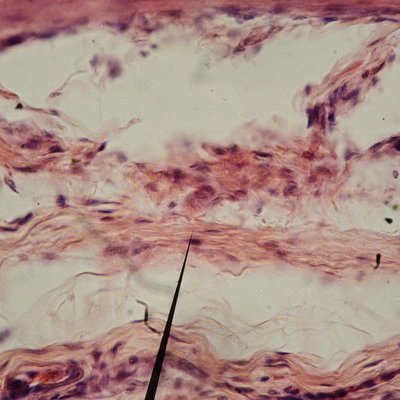

Фото: commons.wikimedia.org/Juan Carlos Fonseca Mata (Creative Commons Attribution-Share Alike 4.0 International license)